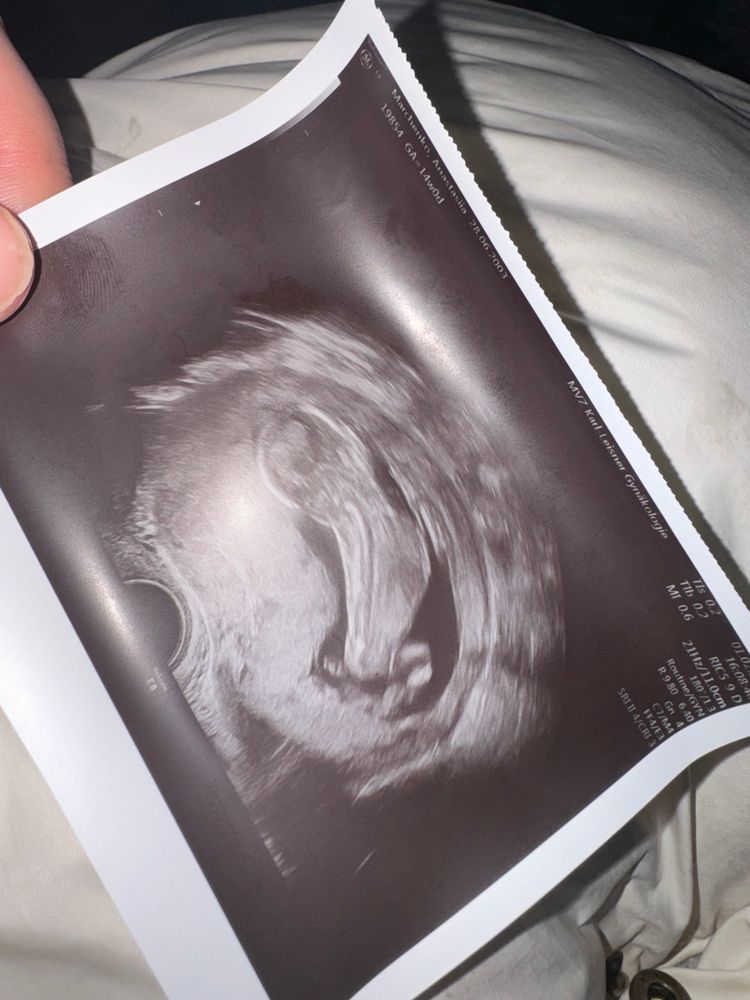

УЗи 14 недель

Такой снимок. Но так или иначе ребенок растет и занимает все пространство внутри.

В 14 недель уже никто и не мерит плодное яйцо

Нарушение кровотока 1 В степень… Тазовое предлежание